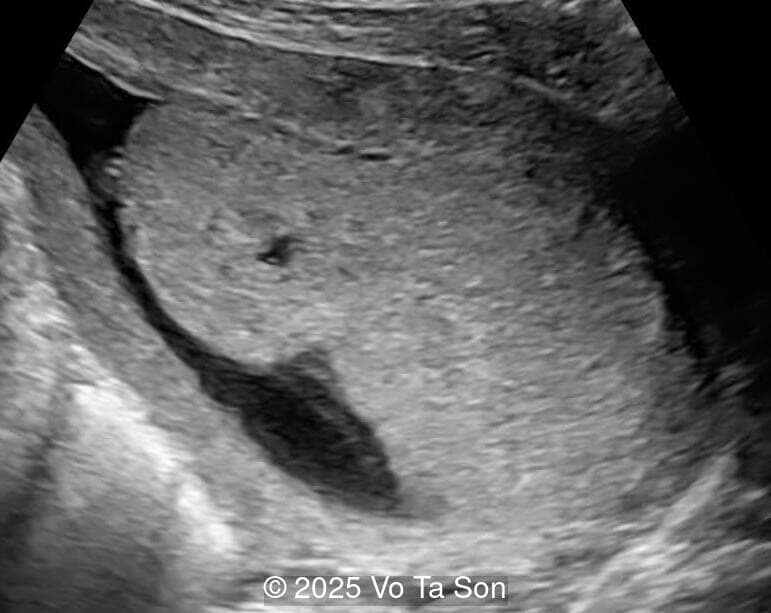

- Cystic-appearing placenta, suggestive of partial molar changes